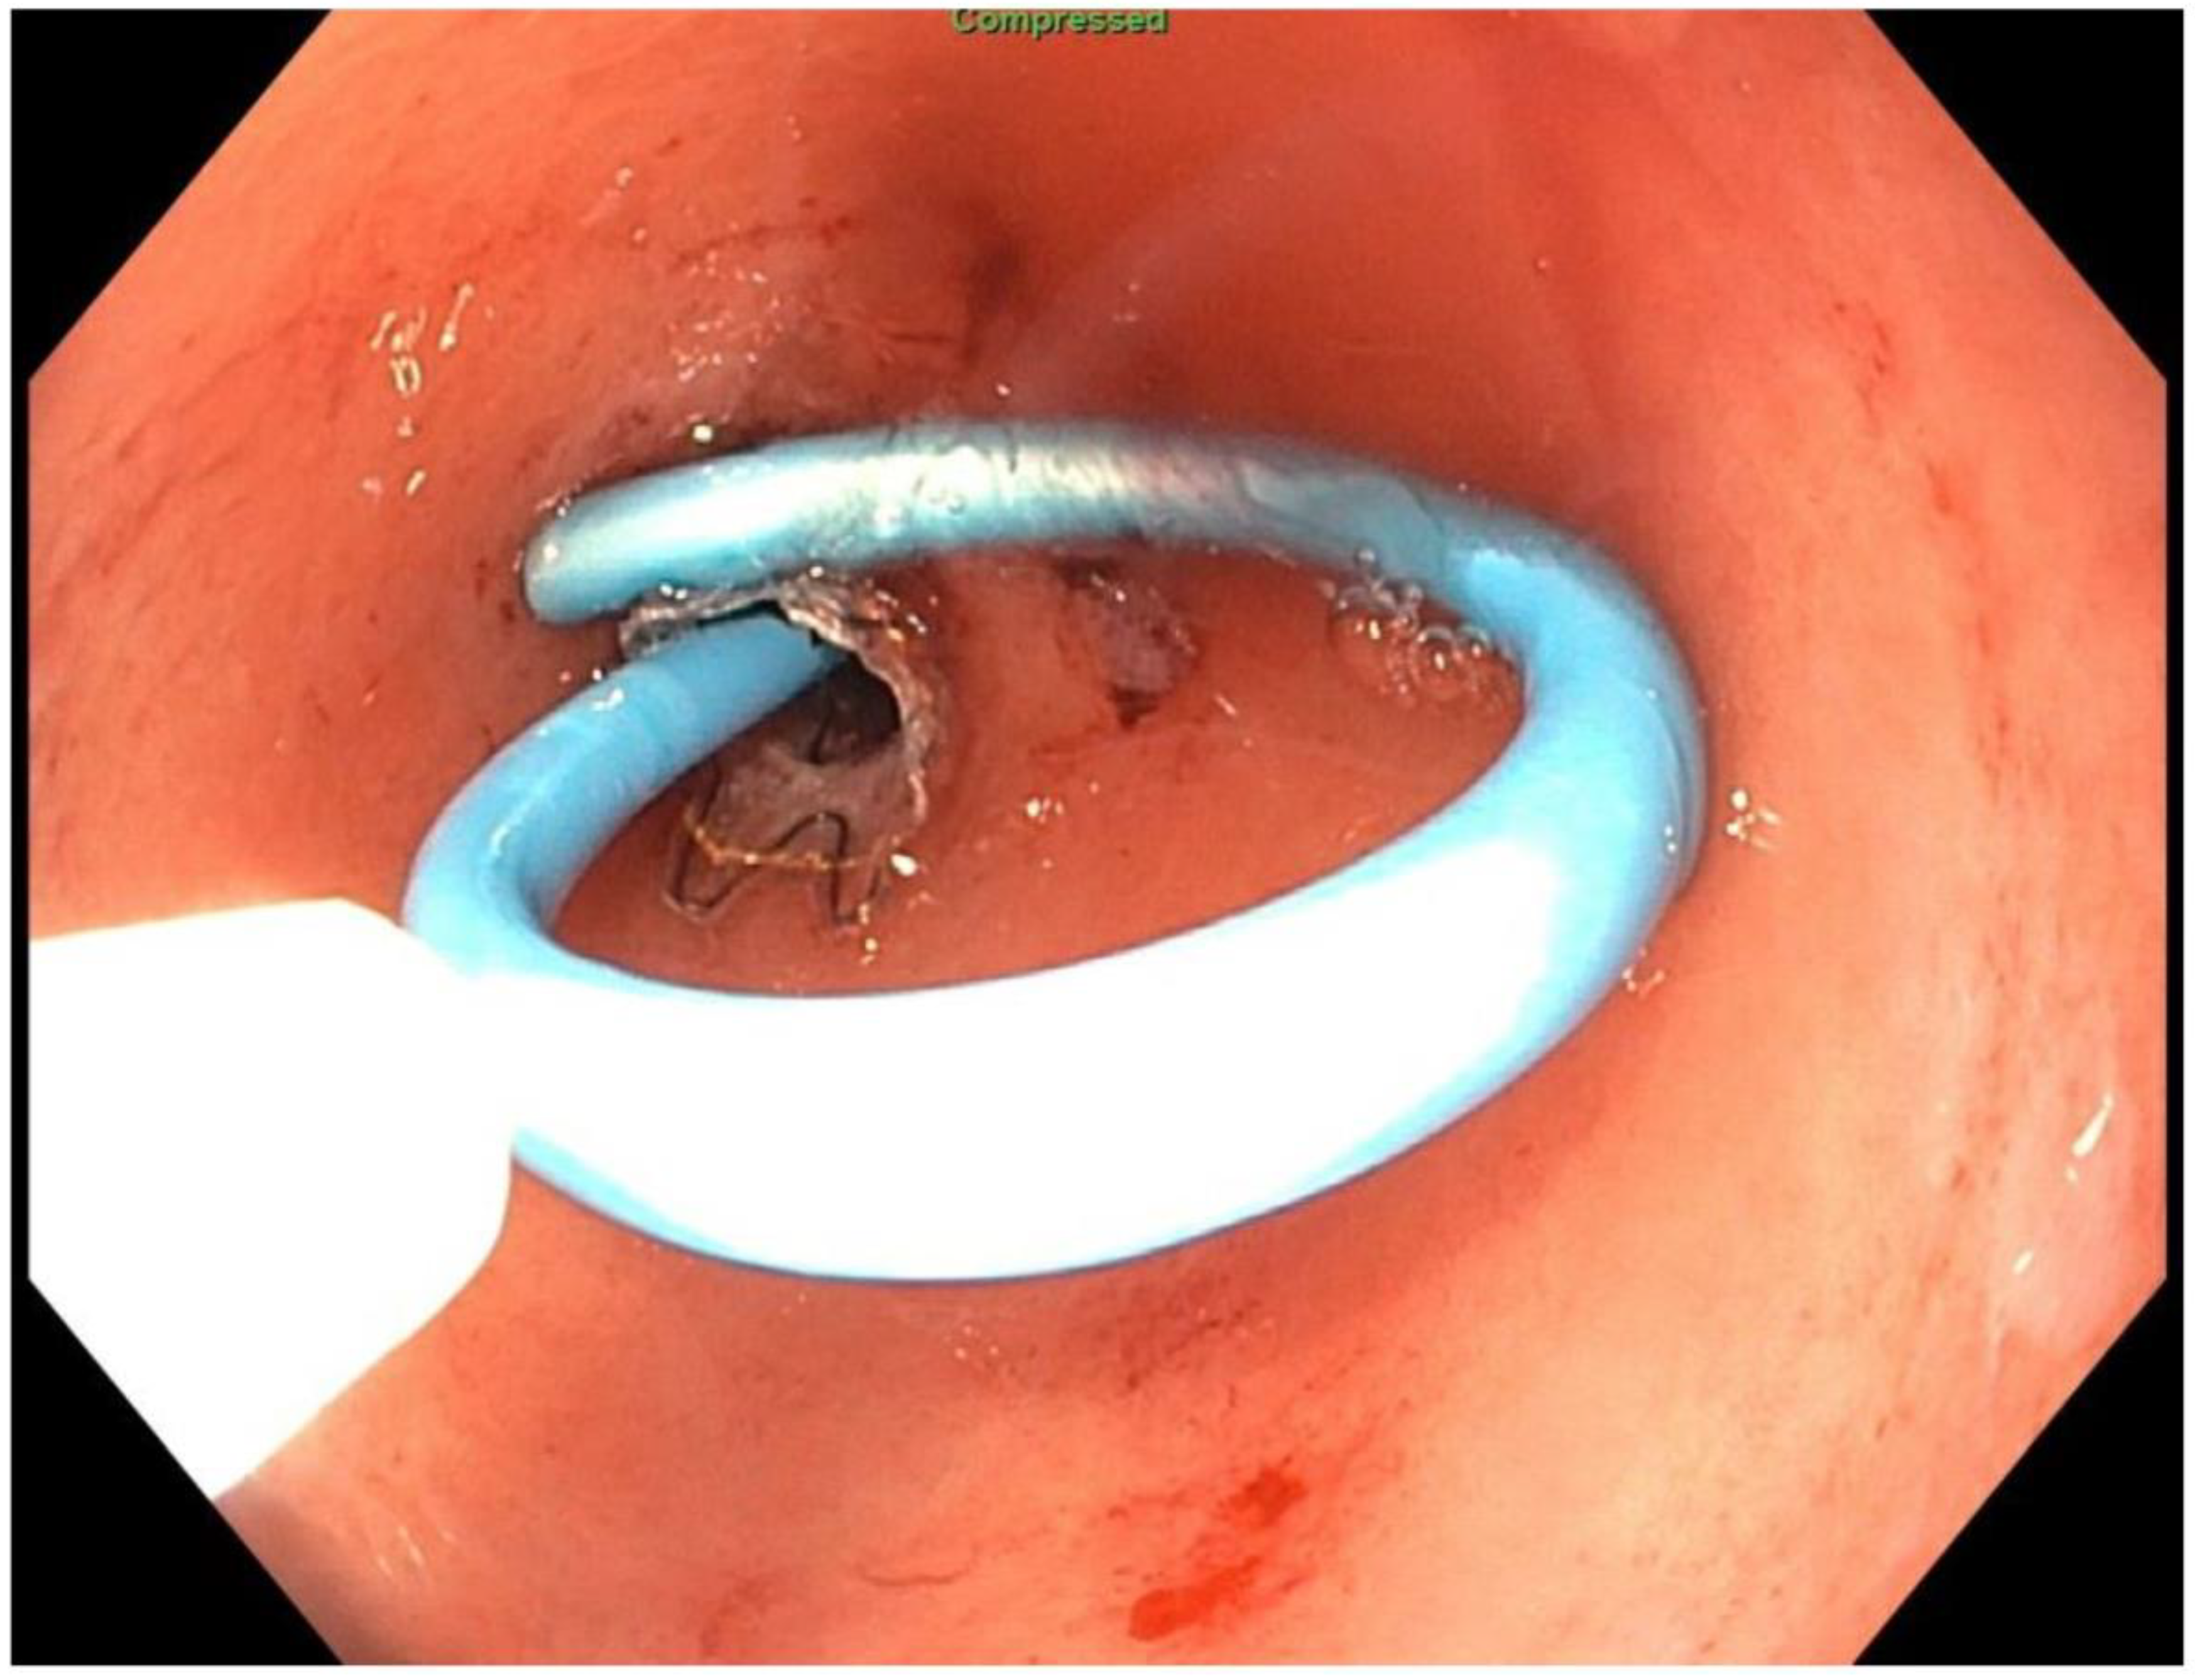

2. Detailed Case Description